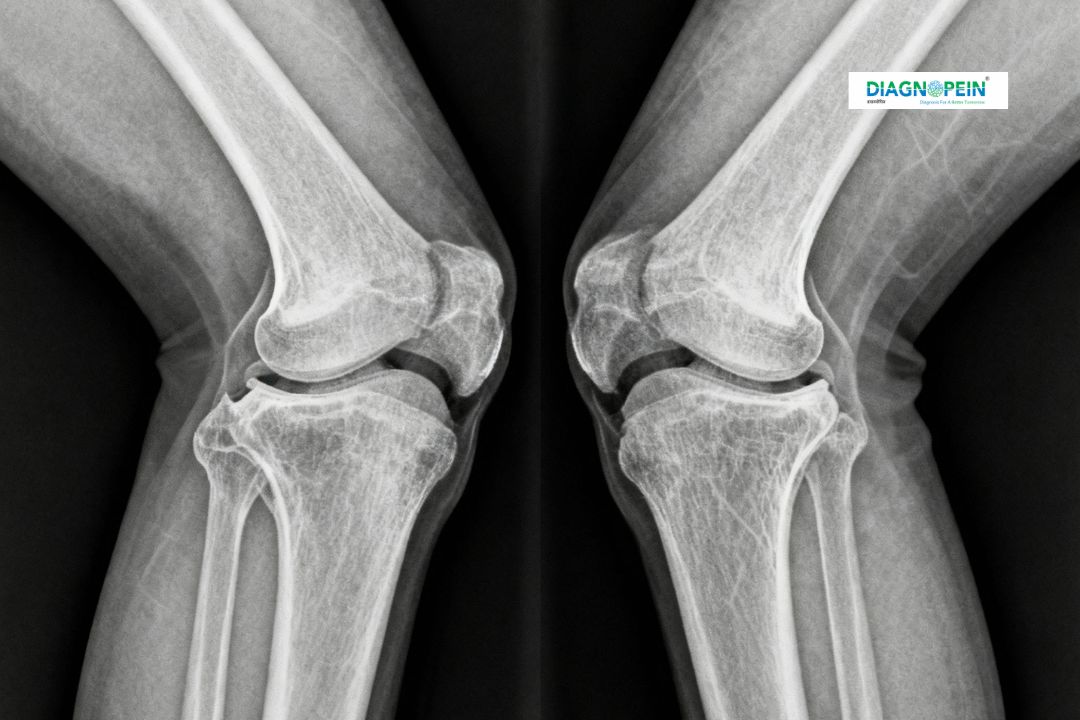

X-ray Both Knee Valgus View is a specialized diagnostic imaging technique used to assess the alignment and structure of both knees, particularly focusing on the valgus angle—the inward bending of the knee joint. This view helps orthopedic doctors identify deformities, joint space narrowing, fractures, or misalignment in both knees simultaneously. Diagnopein in karad provides precise X-ray imaging using advanced radiographic equipment to ensure maximum clarity and accuracy.

The X-ray Both Knee Valgus View plays a key role in identifying abnormalities that cannot be seen through a standard anteroposterior (AP) or lateral knee X-ray. The valgus (knock-knee) angle reveals misalignment issues that could stem from arthritis, injury, or congenital conditions.

At Diagnopein karad, we use this test to evaluate knee joint deformities, detect the severity of valgus deviation, and assist orthopedic surgeons in planning corrective procedures such as osteotomy or joint replacement. This X-ray view also provides comparative data for both knees, enabling accurate diagnosis and treatment planning for gait correction, postural assessment, and chronic knee pain.

At Diagnopein karad, the X-ray Both Knee Valgus View procedure is quick and painless. Patients are positioned in a standing or supine posture depending on the doctor’s instructions. Both knees are aligned to capture the valgus angle under load-bearing or non–load-bearing conditions. The radiographer ensures that the X-ray beam passes through both knee joints, clearly depicting the femur-tibia relationship.

Key parameters evaluated include:

1. Valgus angle measurement (alignment between thigh and shinbone)

2. Joint space assessment for cartilage degeneration

3. Bone density and cortical outline

4. Symmetry comparison of both knees

The entire process takes less than 10 minutes, and results are reviewed by our expert radiologists in karad, who provide digital reports for quick access by referring physicians or orthopedic surgeons.